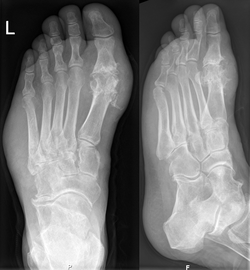

Stvaranje kristala mokraćne kiseline usko je povezano s gihtom. Giht se može dijagnosticirati i liječiti bez daljnjih pretraga ako osoba boluje od hiperuricemije i klasične podagre. Potrebno je učiniti pretragu sinovijalne tekućine, samo ako se sumnja u postavljenu dijagnozu.[3] Premda je rentgensko snimanje korisno pri dijagnosticiranju kroničnog gihta, njegova uporaba pri akutnim napadima nije od velike koristi.[6]